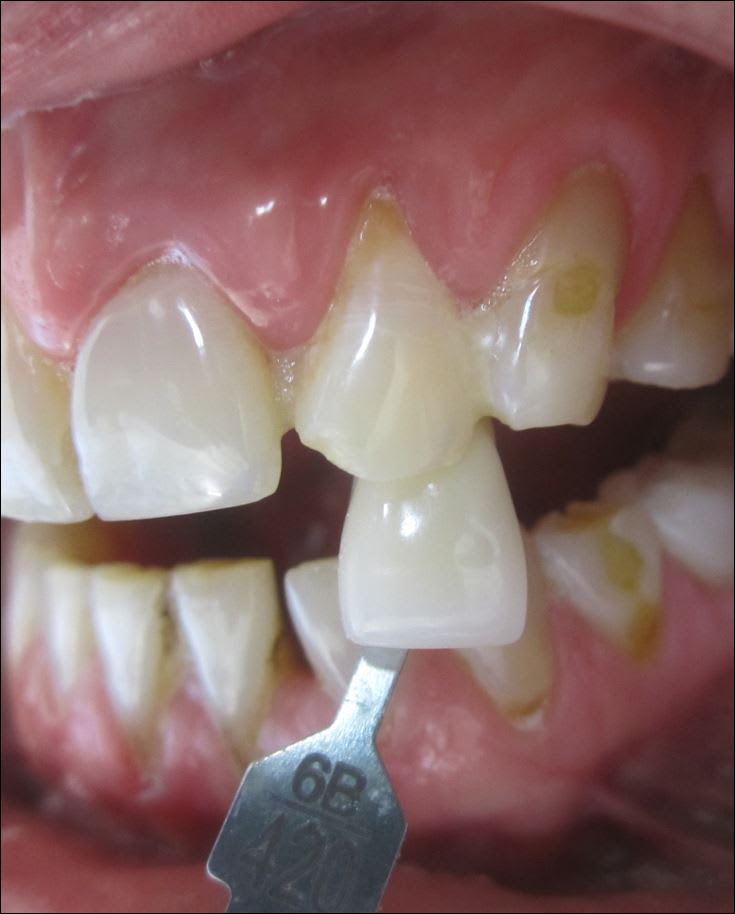

Je le vois en décembre 15j après le trauma pour faire le bilan. Puis un collage /contention sur 22 fracturée et cone beam. Brossage compliqué car grosses douleurs

extraction implant 3mmx14

1° est-ce que vous apporteriez d'emblée du conjonctif pour éviter l'affaissement de la gencive?

2° provisoire sur l'implant ou bridge à ailettes pour temporiser?

le petit bonus la fracture de l'apex de 11 jusqu'ici passée inaperçue vu les douleurs de l'autre côté.